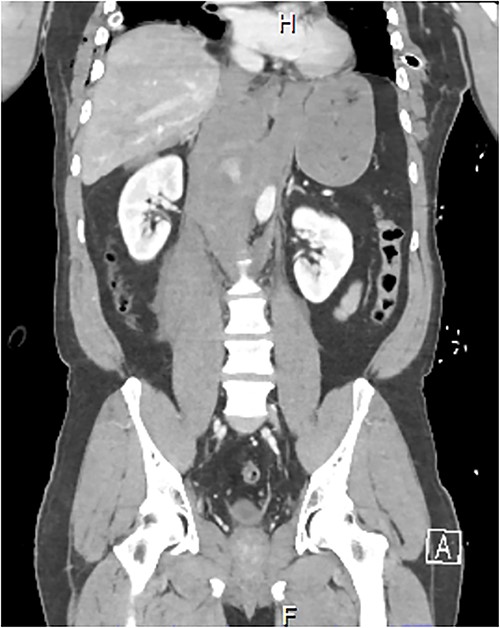

A 54-year-old male presented to our Level 1 Trauma Centre following a high-speed motor vehicle accident with rollover. Although initially haemodynamically stable, significant hypoxia prompted a trauma call activation. On arrival to the Trauma Centre, he had a Glasgow Coma Scale of 8 with an initial heart rate of 70 bpm and systolic blood pressure of 101 mmHg. A brief loss of cardiac output resulted in intubation, bilateral finger thoracostomies and the commencement of massive transfusion. Although his abdominal eFAST was positive, he was fluid responsive and proceeded to imaging. A full computed tomography (CT) trauma series demonstrated CA avulsion (Fig. 1) with contrast extravasation into the retroperitoneum and a large retroperitoneal haematoma measuring 18 cm by 9 cm (Figs 2 and 3). Nil visceral injury was identified and imaging otherwise revealed fractures of the left scapula, right 12th rib and bilateral acetabula and pubic rami.

Coronal CT slice demonstrating coeliac trunk avulsion with active bleeding into a large retroperitoneal haematoma.